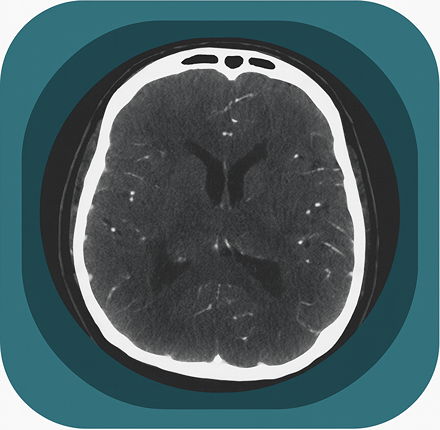

Explore full-body CT anatomy in 3 planes. Our high-resolution, carefully labelled images reveal micro-anatomy—ideal for radiologists, radiographers and surgeons.